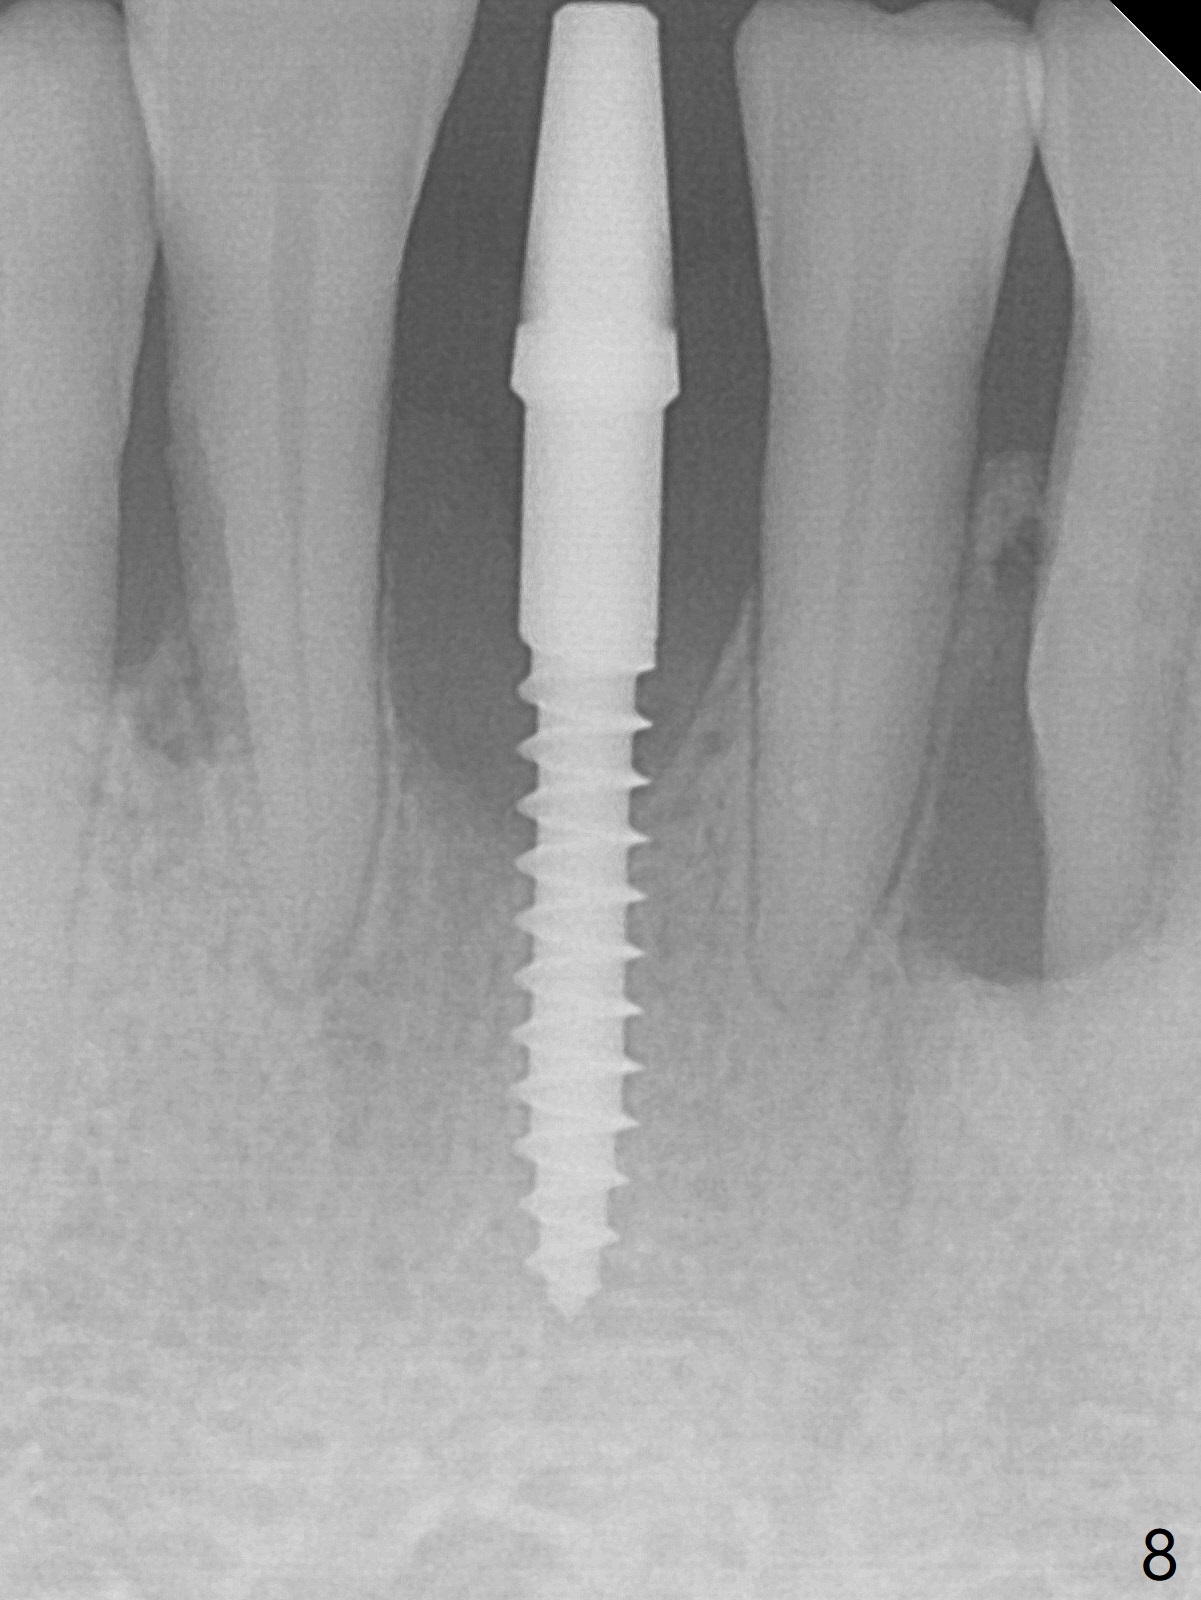

There is gingival inflammation at #25 buccally (Fig.1) and lingually (Fig.2). The bone loss is severe (Fig.3). Soft and hard tissue heights are 5 mm (cuff will be 4 mm) and 10 mm (implant will be 12 mm with 2 mm outside the native bone, Fig.4). The apex of the affected tooth appears deviated distal (Fig.5 *). The initial osteotomy happens to follow the long axis of the socket (Fig.6); to establish a correct trajectory, a new osteotomy should be made at the site labeled as a red line. In fact it is executed as planned (Fig.7). Because of the narrow flat ridge buccolingually, a 2.5x12(4) mm 1-piece implant is placed with >40 Ncm (Fig.8). With deeper placement of the implant, Vanilla graft is placed in 2 steps (Fig.9,10). The patient will return 2.5 months for extraction and implant of the fused teeth #22 and 23. No implant threads are exposed 10 months postop (Fig.11). CT taken 11 months postop shows that the 2.5 mm implant is in the middle of the bone (Fig.12) or 2 years post cementation (Fig.13).